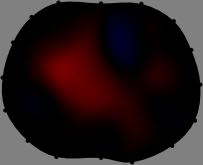

for [23]. This shows that the column vector is like an EEG (electroencephalography) data induced by dipole sources with directions at locations . Given that two dipole sources at distant locations produce mutually independent data, the correlation between and decreases with the distance between and . Fig. 2 shows a few images of the correlation as a function of for four different positions . The correlation decreases rapidly as the distance increases. In the green regions where the correlation is almost zero, is nearly orthogonal to .

Fig. 2 shows that if and are far from each other, the corresponding columns of the sensitivity matrix are nearly orthogonal. This somewhat orthogonal structure of the sensitivity matrix motivates an algebraic formula that directly computes the local ensemble average of conductivity changes at each point using the inner product between changes in the data and a scaled sensitivity vector at that point: